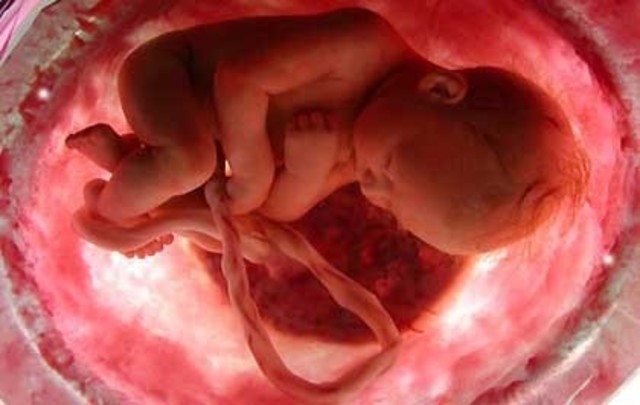

• 4 meses. Características externas

4 meses. Características externas

-La piel es delgada, traslúcida, es fácil ver los vasos sanguíneos debajo de ella

-Las narinas están casi formadas

-El feto puede comenzar a chuparse el pulgar

-Los ojos se han despalzado hacia la parte frontal de la cara

-Las piernas son más largas que los brazos

-Aparece un lanugo fino en el cuero cabelludo

-Las uñas de la mano están bien formadas; se están formando

las de los pies

-Aparecen los pliegues epidérmicos en los dedos

-La madre puede sentir los movimientos fetales

• 4 meses. Características internas

4 meses. Características internas

-Se forman las vesículas seminales

-Aparecen los surcos transversos en la superficie dorsal del cerebelo

-Se produce bilis en el hígado y tiñe de verde al meconio

-Las glándulas gástricas hacen gemacióna partir de las fóveas gástricas

-Comienza la hematopoyesis en la médula ósea

-Los ovarios contienen folículos primordiales